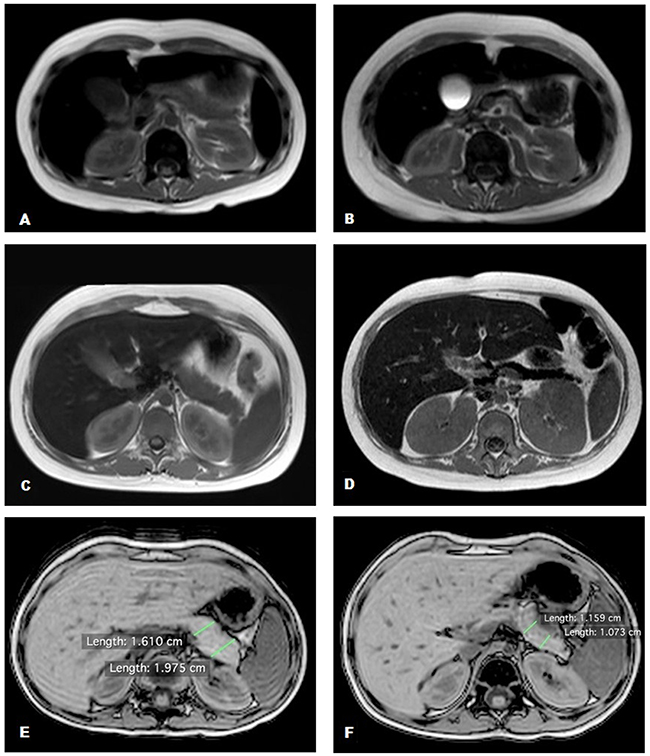

Baseline and post-transplantation pancreatic volumes were compared in the two groups. The mean pancreatic volume reduction was significantly higher in the TBI group (39.1% vs 0.9% in the MCHT group; p<0.05). Patients in the TBI group, who underwent DFO chelation therapy, had the highest mean volume reduction from 31.8 cm3 to 16.2 cm3, corresponding to a mean reduction of 49.2% (p<0.01) with a maximum reduction of 61.9% and minimum of 36.3%. Patients in the group without DFO chelation therapy had a lower mean volume reduction from 30.2 cm3 to 20.9 cm3, corresponding to a mean reduction of 31.2% (p<0.01) with a maximum reduction of 40.1% and minimum of 19.3%. The difference in the decrease of pancreatic volume between the two groups was statistically significant (p<0.01). Images of the two most impressive cases of acute pancreatic IO with reduction of pancreatic volume are shown in Figure 1A–1D.

Figure 1: Abdominal MRI T2 fast field echo sequences. (A, C, E) Normal pancreas signal and volume; (B, D) hypointense pancreas signal with reduction of pancreatic volume; (F) normal pancreas signal with a reduction of pancreatic volume.

To assess the role of TBI in pancreatic shrinkage, we scheduled an MRI scan at 48–72 hours after the last TBI session for the last three patients treated. All patients had a significant pancreatic volume reduction. The first patient had a reduction of 30.2% (20.9 cm3vs 14.6 cm3 baseline volume at 48 hours after TBI), the second patient had a reduction of 36.6% (21.3 cm3 vs 13.5 cm3 baseline volume at 72 hours after-TBI), and the third patient had a reduction of 35.4% (36.2 cm3 vs 23.4 cm3 baseline volume at 72 hours after TBI). The PICs of all three patients remained unchanged in the first 48–72 hours after TBI (Figure 1E, 1F).